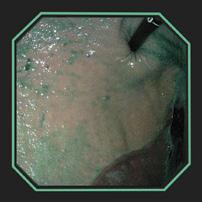

VISUALIZING SLIMER AT WORK

DISTRIBUTION OF SLIMER THROUGHOUT SQUAMOUS AND GLANDULAR REGIONS

DISTRIBUTION OF SLIMER (without color dye) SHOWING PRODUCT GRANULARITY

The above gastroscopy images show Slimer coating the stomach. The horses received 2oz of Slimer via syringe and then lunged at the walk and trot for 10-15 minutes to simulate splashing acid while being ridden. Though Slimer is brown, it was initially dyed blue to be more visible. In order to show that the blue dye did not discolor the stomach or disassociate from Slimer, over 90cc of water was inserted through the gastroscope to “rinse” a portion showing that the underlying tissue remained pink.

DEMARCATION AREA RINSED WITH WATER HIGHLIGHTING SLIMER’S GRANULARITY

DISTRIBUTION OF SLIMER (without color dye) THROUGHOUT SQUAMOUS AND GLANDULAR REGIONS